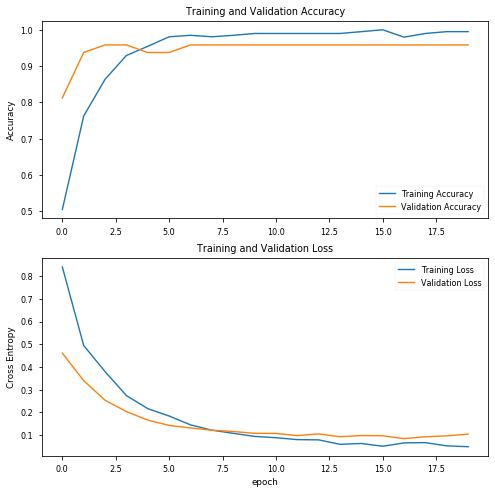

使用20个阶段和初始参数,结果看起来非常有趣,验证数据的精度达到100%!让我们绘制精度图表,评估训练的模型,并查看混淆矩阵:

结果完全令人满意,因为只有4%的患者没有Covid会被误诊,但与本例一样,肺炎患者和Covid-19患者之间的正确分类是最有益处的,因此我们至少应该对超参数进行一些调整,再次进行训练。

第一件事,我试图降低最初的lr一点点,然而效果并不好,所以我恢复了原值。

我还减少了数据的分割,稍微增加了Covid图像,并将最大旋转角度更改为10度,这是在与原始数据集相关的论文中建议的:

INIT_LR = 0.0001 EPOCHS = 20 BS = 16 NODES_DENSE0 = 128 DROPOUT = 0.5 MAXPOOL_SIZE = (2, 2) ROTATION_DEG = 10 SPLIT = 0.1

因此,我们有:

precision recall f1-score support covid 1.00 1.00 1.00 13 pneumo 1.00 1.00 1.00 14 accuracy 1.00 27 macro avg 1.00 1.00 1.00 27weighted avg 1.00 1.00 1.00 27

以及混淆矩阵:

[[13 0] [ 0 14]]acc: 1.0000sensitivity: 1.0000specificity: 1.0000

结果看起来更好,但我们使用了很少的测试数据!让我们保存模型,并像以前一样用大量图像对其进行测试。